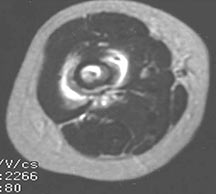

- Radiographically variable appearance: may appear benign (geographic) or malignant (permeative or moth eaten)

Radiographic Presentation